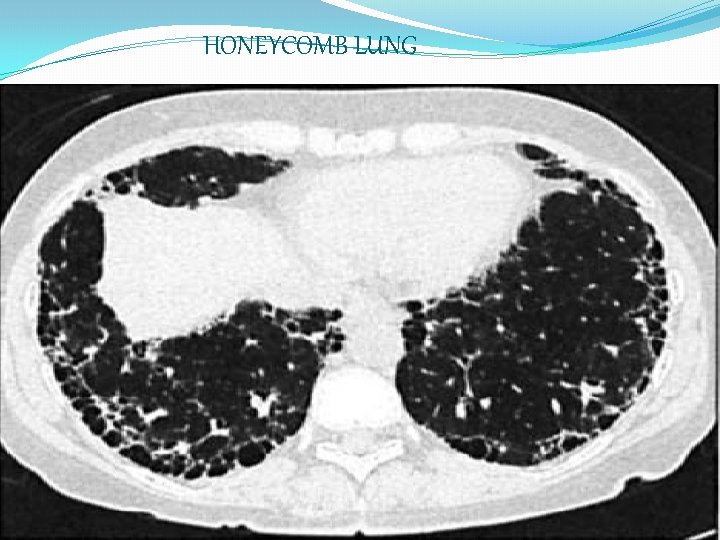

HRCT �Ground glass appearance �Reticulonodular shadowing �Honey-comb lung-small, uniform sized, cystic spaces representing patent bronchioles �Traction bronchiectasis �Provides quantitative assesment of pulmanary fibrosis

HONEYCOMB LUNG

Hrct of ipf On HRCT, a confident diagnosis of IPF is based on the presence of bilateral, predominantly subpleural, and basal reticular opacities with associated traction bronchiectasis and honeycombing in the absence of small nodules or extensive ground-glass opacity. this is known as “confident” pattern of IPFon HRCT.